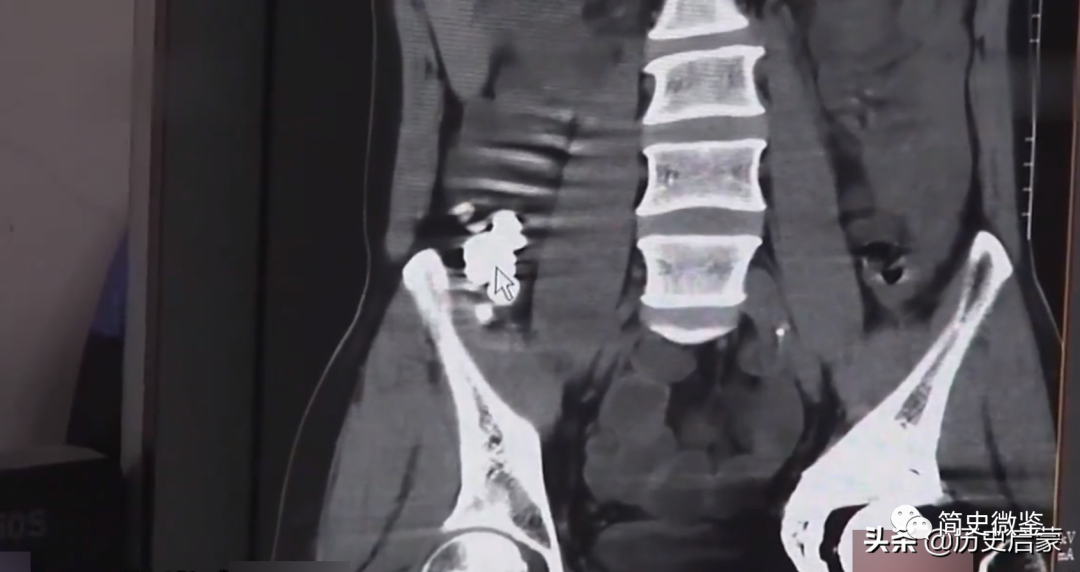

大家都觉得有道理,于是,押着侯东平来到了揭阳市产业园人民医院,做腹部CT检查。这一查,果然印证了民警的猜想。

CT影像里,在结肠部位,可以清晰的看到一串形态像珠子的高密度的东西,数量有几十颗,每颗的直径大约1.2公分,不是那串项链还会是什么?

珠子已经堵住了消化道,如果不及时取出,将会导致肠梗阻等并发症,对生命都有危险。在医生的帮助下,终于排出了所有的47颗翡翠珠子。

医院的CT影像